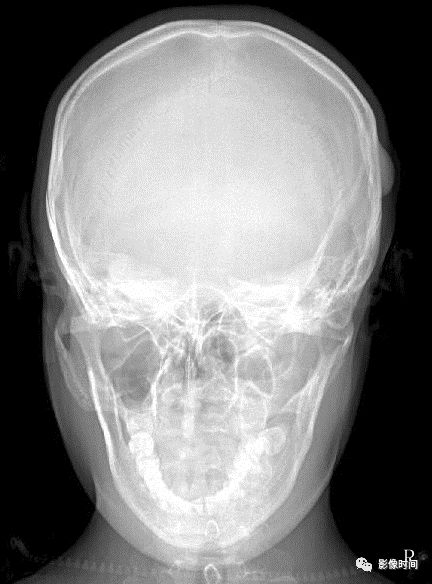

正常骨质被肿瘤或肿瘤样组织代替称骨质破坏。根据骨质破坏的形式可分为地图样破坏、膨胀性破坏、浸润性破坏和压迫性骨质缺损。

(一)地图样破坏  地图样破坏是指肿瘤组织在一个局部呈团块状生长造成界限清楚的骨质破坏(图 1、图 2、图 3、图 4)。

病灶可位于骨的中心或一侧部位,呈圆形、卵圆形密度减低区,与正常骨质分界清晰,边缘可有或无硬化带围绕,骨的形态无变化,病灶内可完全透亮或可见粗细不均、大小不等的残留骨嵴,内缘可光滑或呈分叶状压迹。

地图样破坏见于大多数良性肿瘤和肿瘤样病变如单纯性骨囊肿、骨纤维结构不良、血管瘤等、也可见于部分恶性骨肿瘤如骨转移瘤、骨髓瘤等。

图 1  地图样破坏:单纯性骨囊肿

图 2  地图样破坏:骨纤维结构不良

图 3  地图样破坏:骨内脂肪瘤

图 4 地图样破坏:骨转移瘤